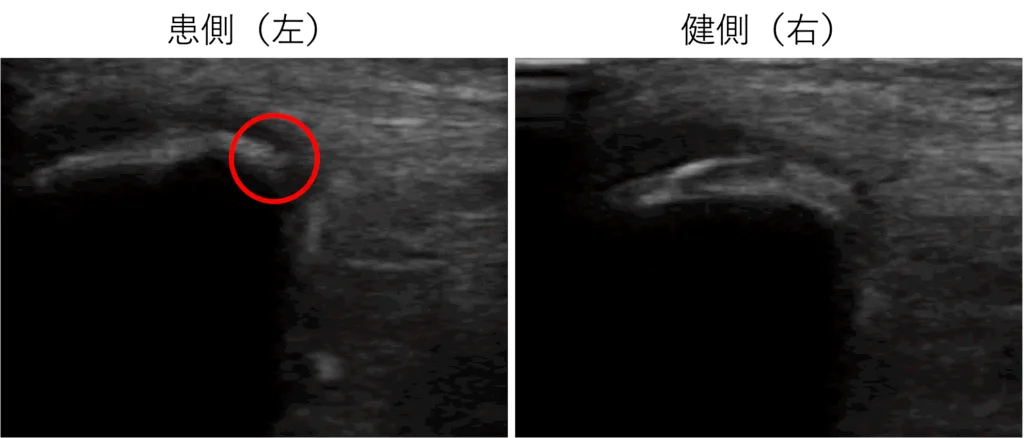

病態把握のため、エコー検査をしたところ、左膝蓋骨の下端部に裂離骨片と思われる画像が描出できました。

膝蓋骨の下端部の症状である「シンディング-ラルセン-ヨハンソン病」(膝蓋骨の成長痛)を疑い、連携病院に紹介しました。